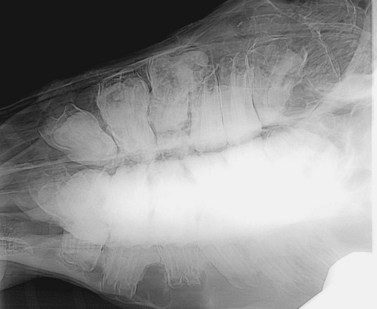

Vertical impaction of cheek teeth (‘eruption cysts’; ‘3 year-old and 4-year-old bumps’)

As noted in the previous section, many horses develop focal, bilateral swellings of their mandible and also less obviously (due to the presence of overlying muscles) of their maxillae beneath the developing apices of the 07 and 08 CT (Fig. 8.28). Certain breeds, especially lighter breeds and miniature breeds in particular, are more prone to develop these bony swellings. These eruption cysts may be due to vertical impaction of the CT that erupt last and a study showed increased angulation of the two adjacent CT onto mandibular CT with apical infection.36 With time, as the mandible and maxillae lengthen, the impacted CT have room to erupt normally and the overlying bones then remodel to a normal contour over the following year or so. Occasionally, the impacted tooth may become ankylosed to the ventral mandibular cortex and never erupt (Fig 8.29).

image image

Fig. 8.29 (A) Diagrammatic representation of overcrowding and vertical impaction of a mandibular 08. (B) Radiograph of a vertically impacted 307 that has become ankylosed to the ventral mandibular cortex. Additionally, marked drifting of the two adjacent teeth (306, 308) more occlusally now permanently prevents its eruption.